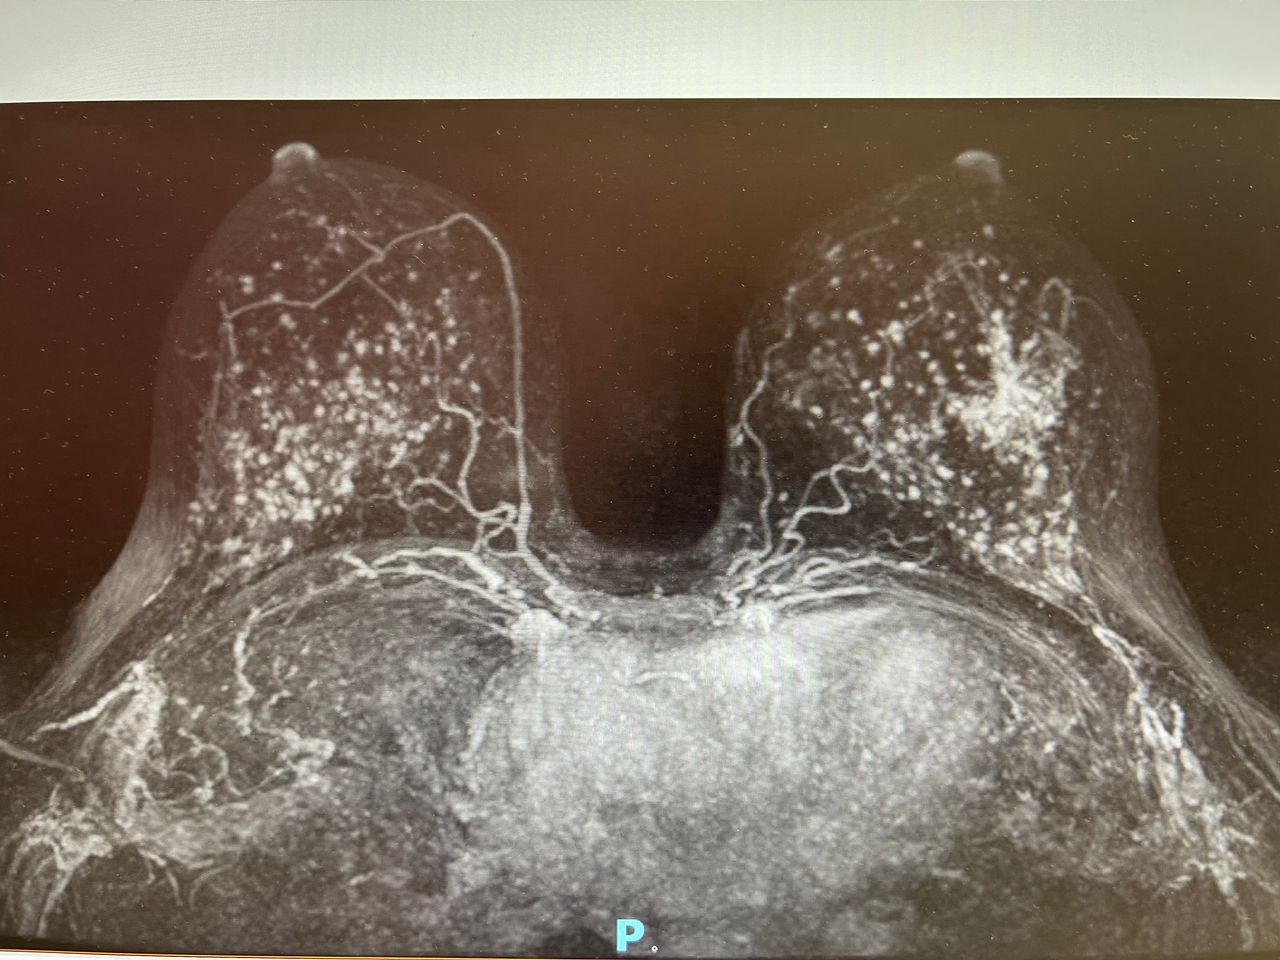

Foto e video